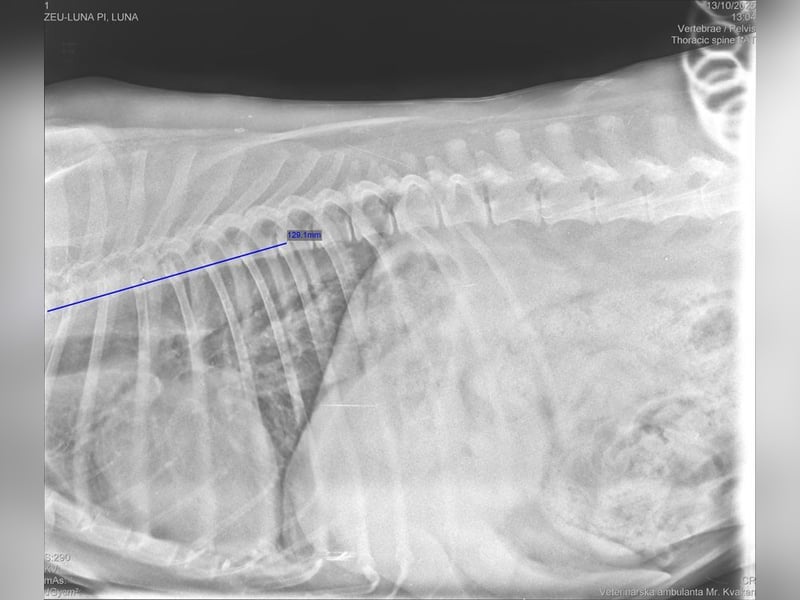

Mitte Oktober 2025 war die Tierheimleitung mit Pi zur vollständigen tierärztlichen Untersuchung in der Tierklinik. Dort wurde festgestellt, dass Pi an der Wirbelsäule Spondylose hat. Pi benötigt Schmerzmittel und zur Unterstützung der Gelenke Flexadin.

In der Bildergalerie befindet sich ein Röntgenbild von der Wirbelsäule. Weitere Röntgenbilder können Sie beim Vermittlungsgespräch von unseren Kontaktpersonen erhalten.